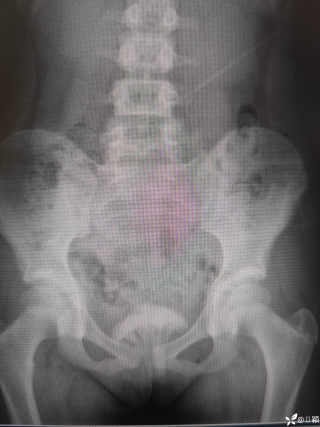

2023年10月26日,来自山东菏泽市成武县的小烨和他家人的命运被彻底改变了。这个原本阳光、可爱的小男孩在一次意外被撞击后,在医院检查出了腹腔内存在肿瘤,并在手术中被切除了包括十二指肠、胰腺、大部分胃和小肠等多个器官。此后便无法再像正常人一样吃饭、喝水,活着要靠长期静脉注射营养液。一份2024年12月由第三方机构出具的司法鉴定意见书显示,当时给小烨做手术的成武县人民医院在该医疗行为中存在过错,与小烨的损害后果之间存在因果关系,建议医疗过错在损害后果中的原因力大小为同等原因。此外,另一份由成武县卫生健康局在2025年9月28日发出的书面答复中显示,成武县人民医院存在24小时内未完成病历;手术知情

豫刀匠秦 回复

医疗无小事,更何况牵涉到孩子,局部获益要让位于整体生存获益,SPT目前划为低度恶性,如果小于3cm可以局部切除,如果大于3cm,在主胰管附近,可以保十二指肠的胰头切除,当然保十二指肠还是要到大中心去,不过SPT应该也没有这么急切,不了解当时情况,无法置评,只能说术前评估有些草率了,当然有可能该县医院技术确实比较强,不过TPN,应该是损伤了SMA,或者SMV大出血缝闭了,不过SMV能修也能接,如果是SMB按理说不至于,只能说一句艺高人胆大!何况儿童手术,当慎之又慎!当下环境,窃以为病不好慎做,病人不好慎做,病人家属不好慎做!救命手术,下台为主!非救命手术,预后为首!炫技无用,又没人给你点赞加薪!